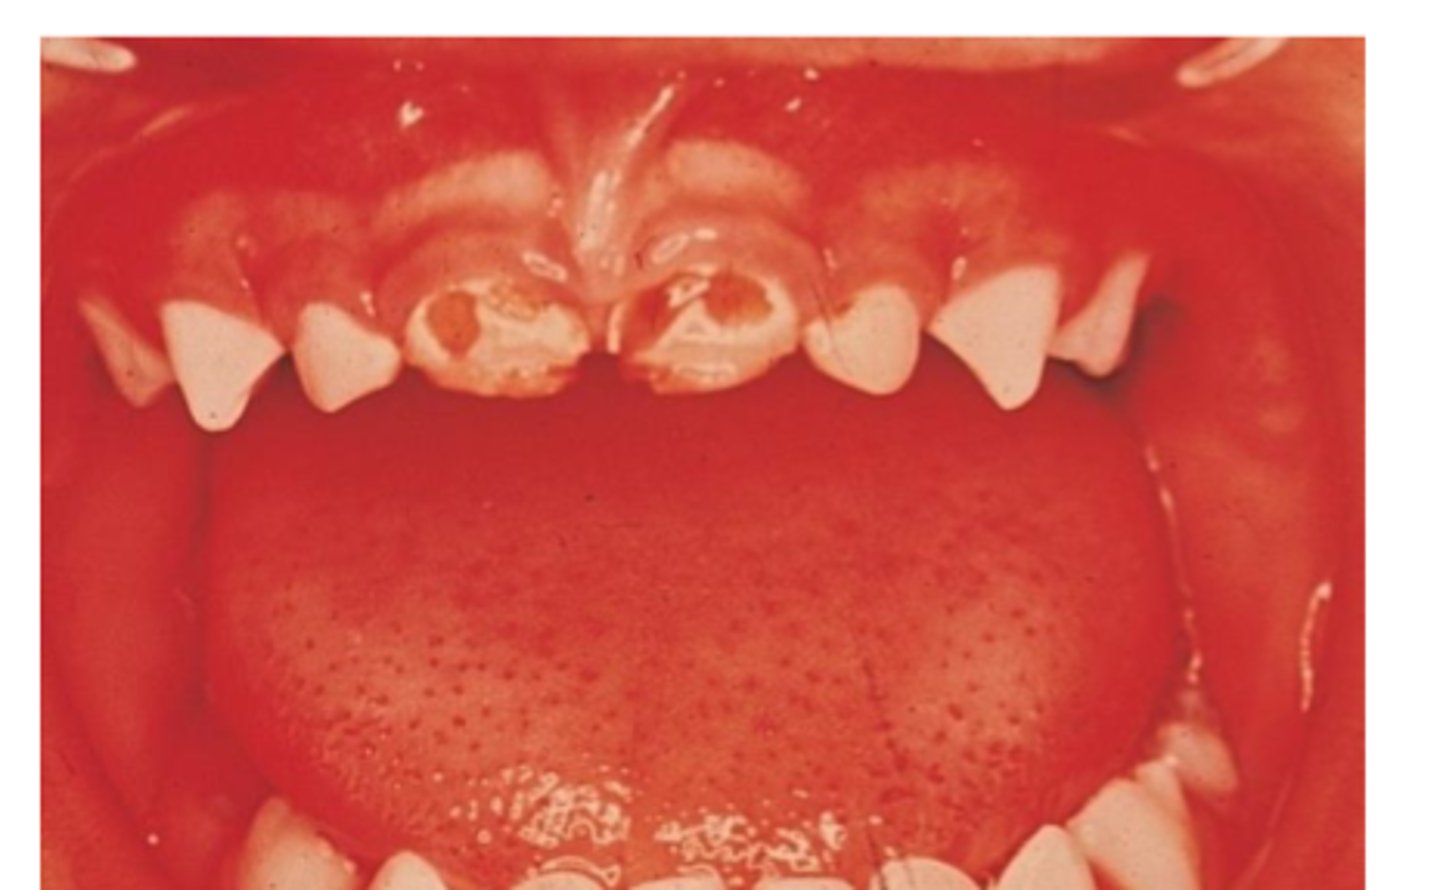

____: can cause rampant caries in todder/infant

baby bottle syndrome